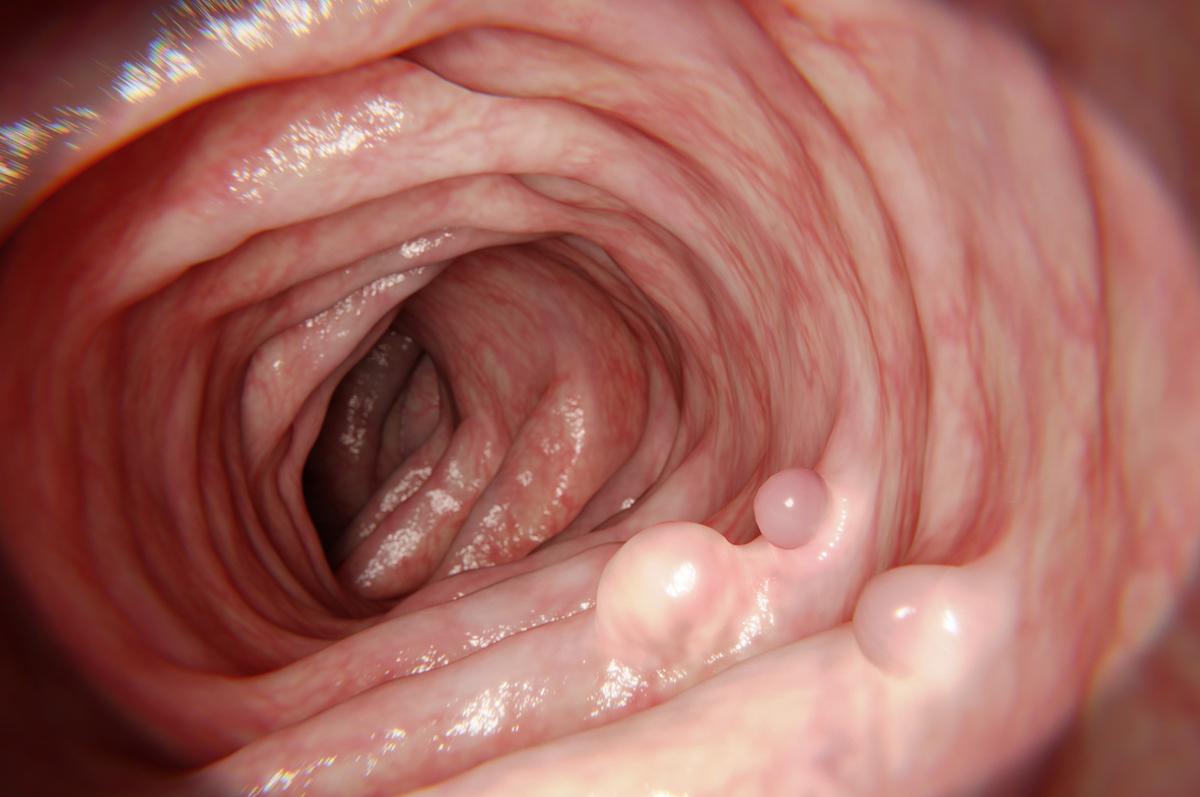

- NataliaDeriabina / istock.